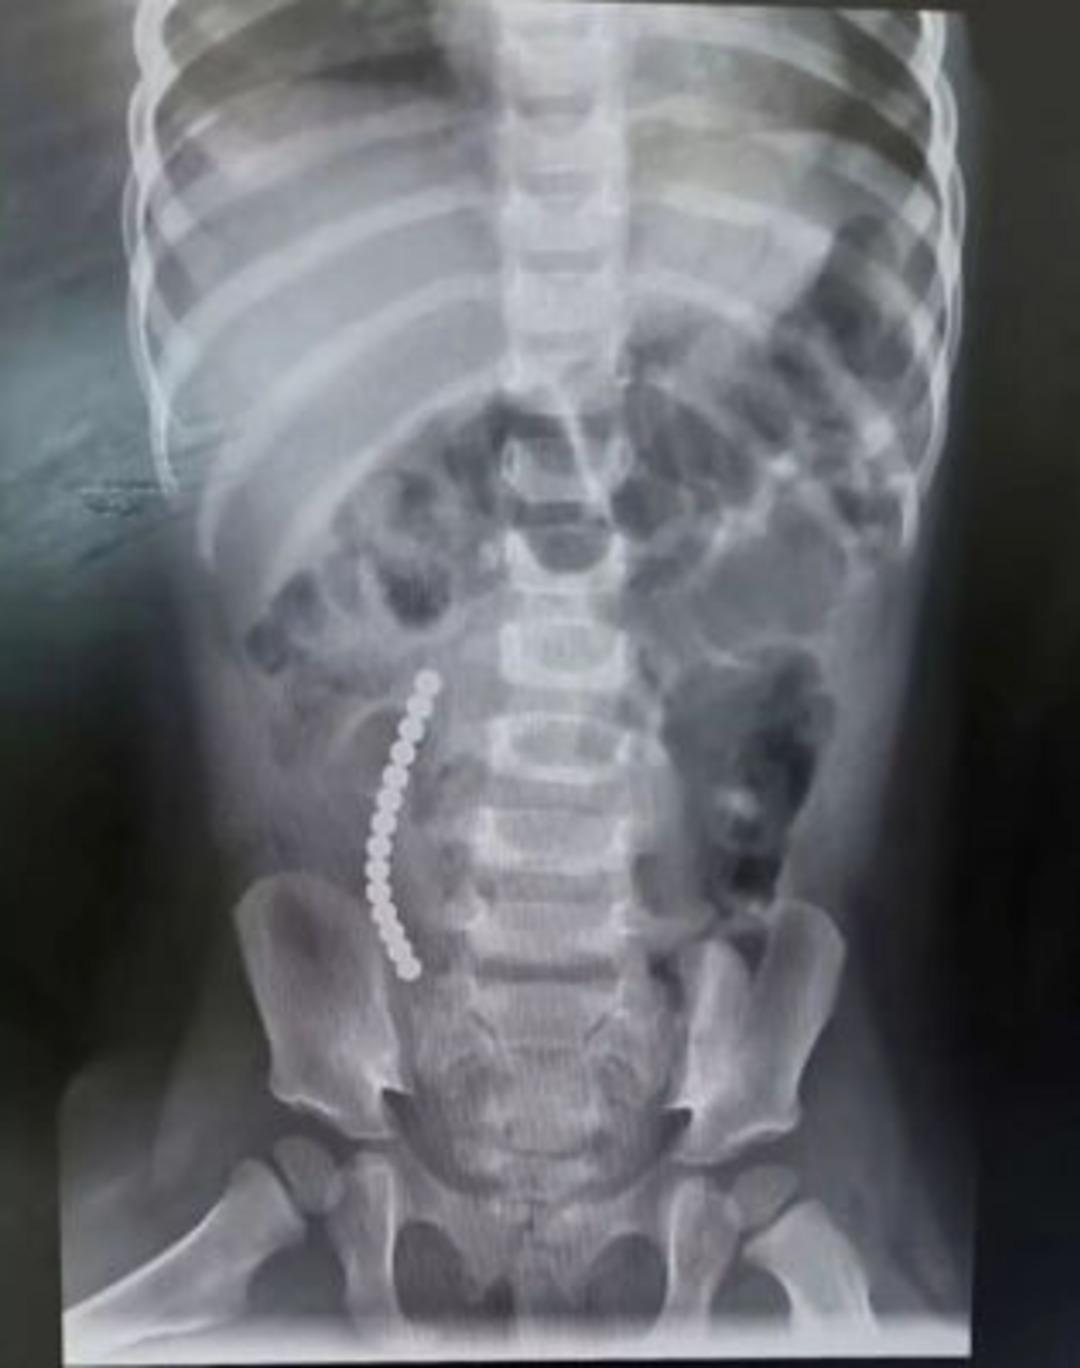

İngiltere’nin Basildon kentinde yaşanan olay dehşete düşürdü. İki yaşındaki Rebecca McCarthy’nin annesi Sam, çocuğunun kusmaya başlamasıyla bir şeylerin ters gittiğini fark etti. Hastaneye kaldırılan çocuğun 14 adet mıknatıs yuttuğu ortaya çıktı.

The Mirror'ın haberine göre ameliyata alınan çocuğun operasyon sırasında bağırsakları dışarı çıkartıldı. Ameliyattan sonra bir dizi sağlık problemi yaşayan küçük çocuğun annesi, internetten satın alınan oyuncakların tehlikelerini vurgulayarak, ''Bizim yaşadıklarımızı kimsenin yaşamasını istemem, bu kaza ailemizi perişan etti'' ifadelerinde bulundu. McCarthy’nin hastanedeki tedavisi sürüyor.